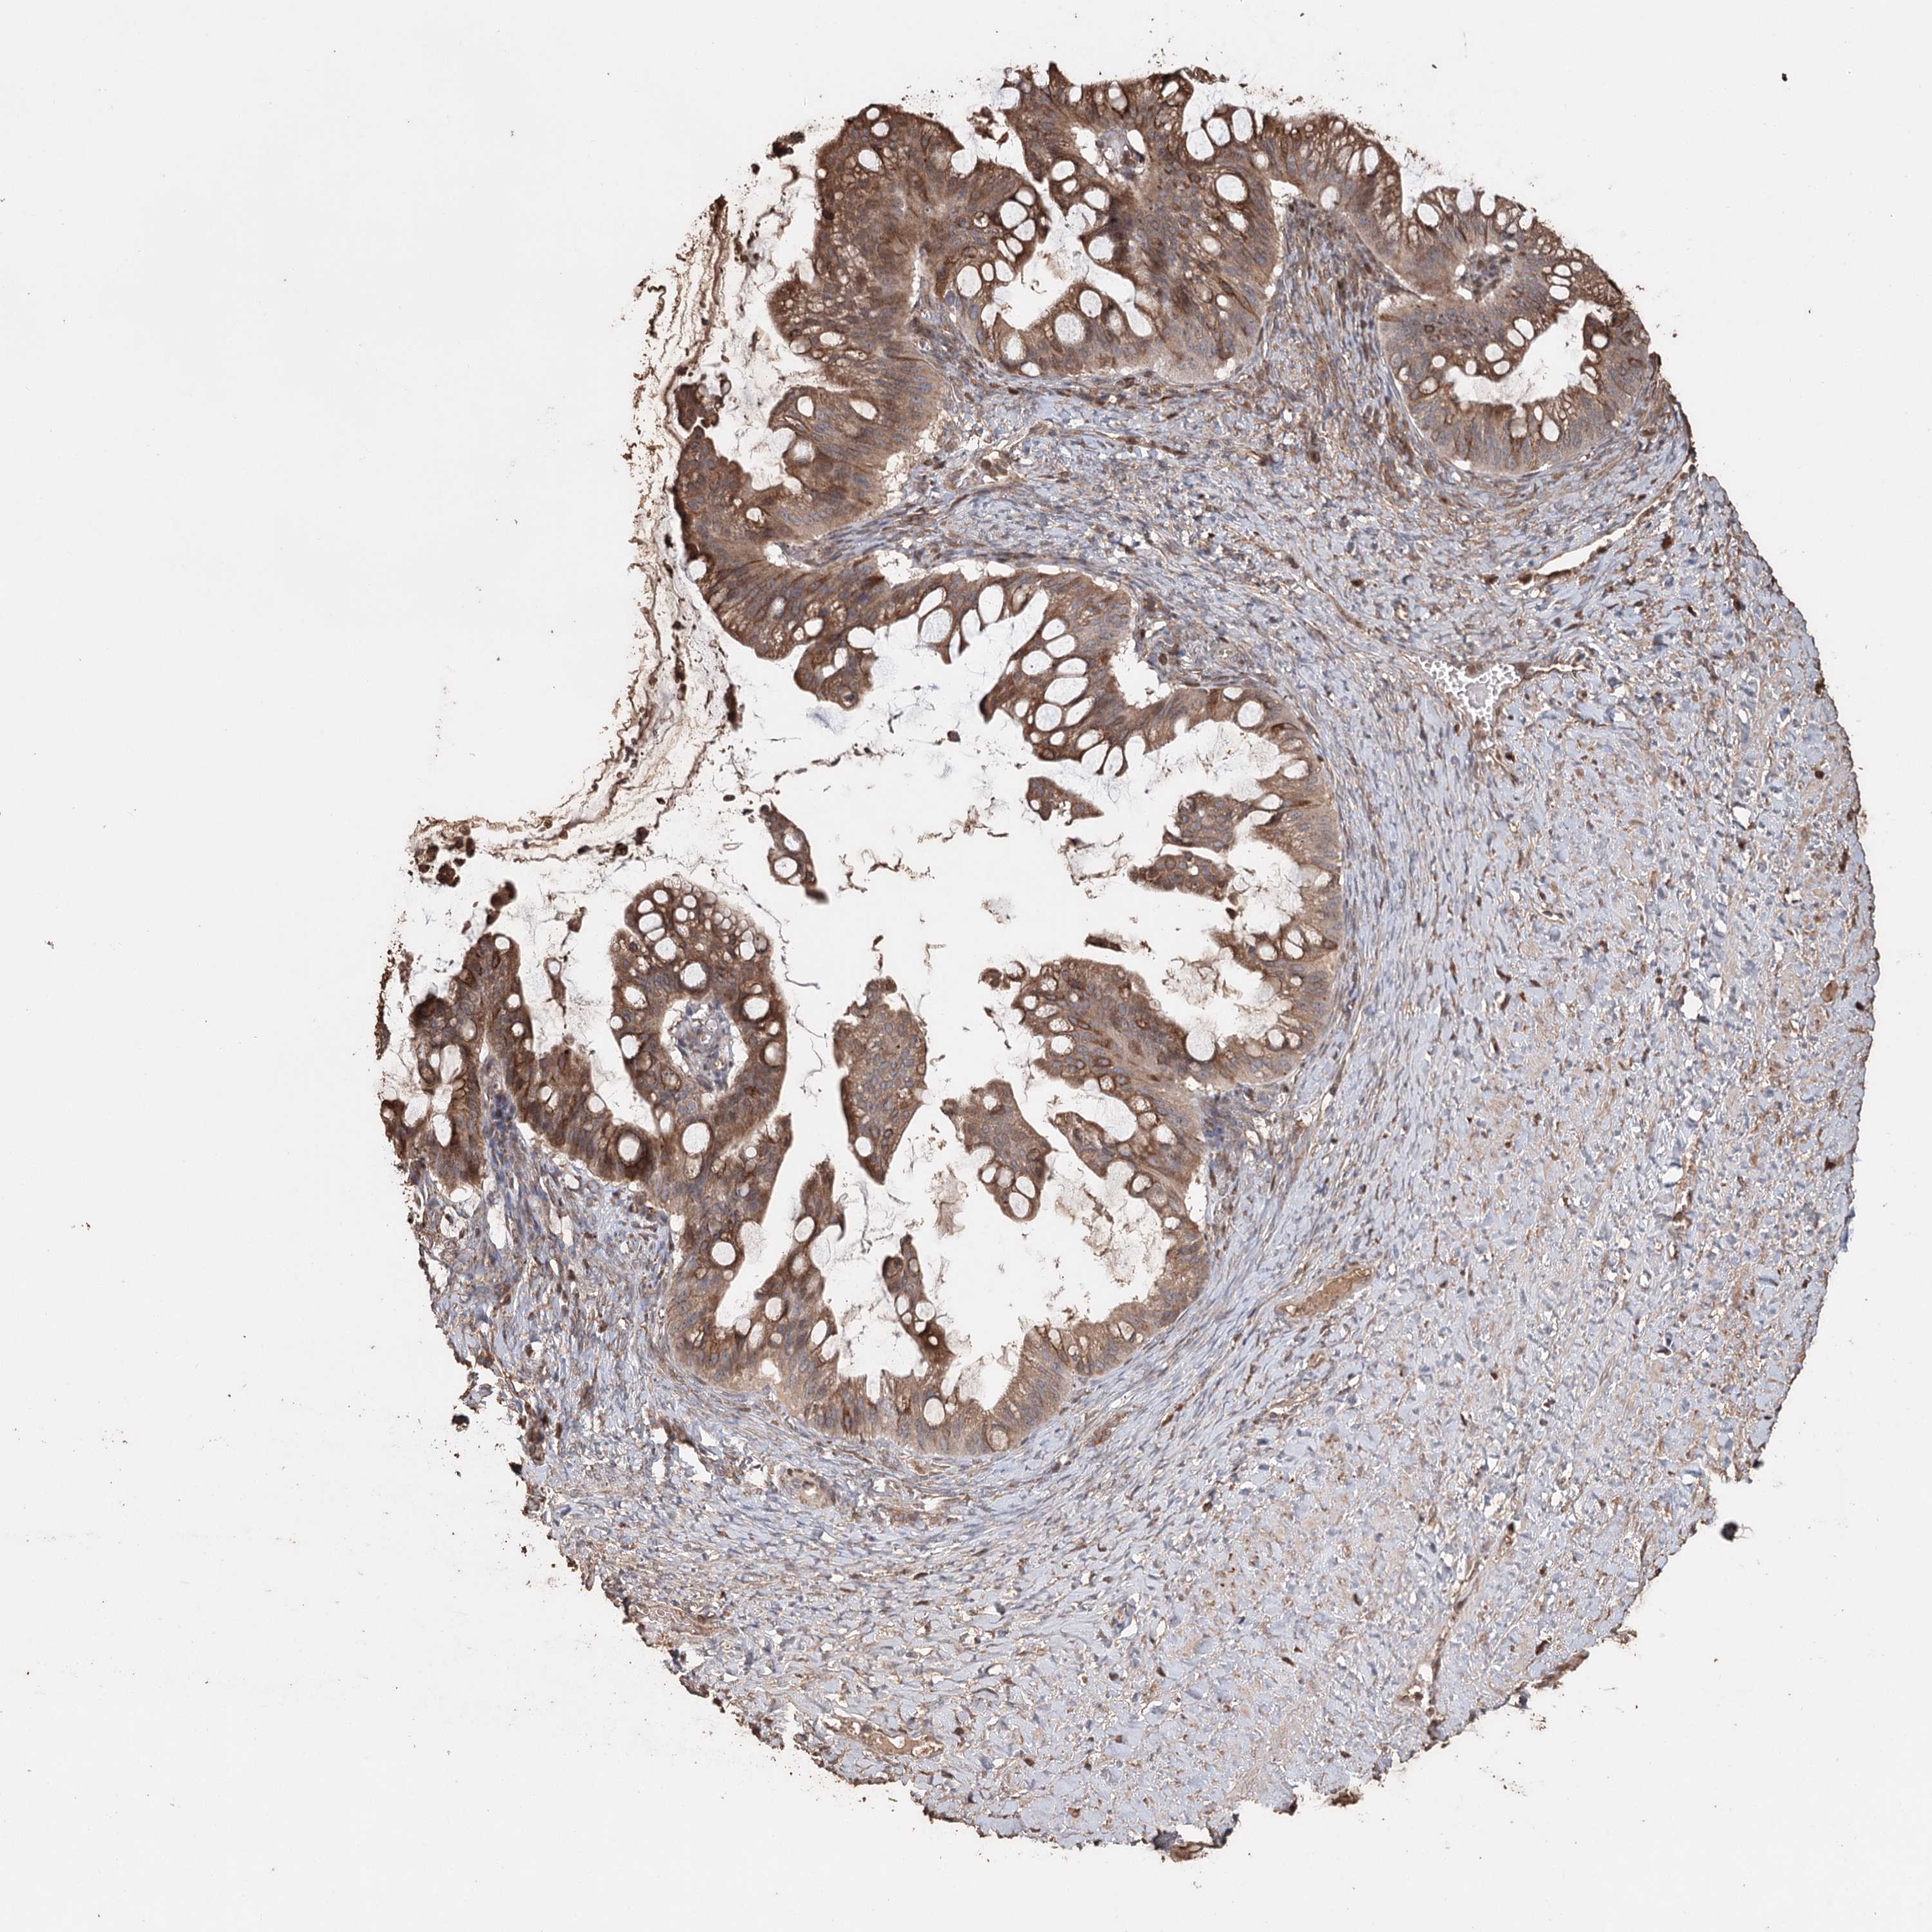

OVARIAN CANCER - Protein expressioni

A mouse-over function shows sample information and annotation data. Click on an image to view it in a full screen mode. Samples can be filtered based on level of antibody staining by selecting one or several of the following categories: high, medium, low and not detected. The assay and annotation is described here.

Note that samples used for immunohistochemistry by the Human Protein Atlas do not correspond to samples in the TCGA dataset.

Antibody stainingi

Antibody staining in the annotated cell types in the current human tissue is reported as not detected, low, medium, or high, based on conventional immunohistochemistry profiling in selected tissues. This score is based on the combination of the staining intensity and fraction of stained cells.

Each image is clickable and will lead to virtual microscopy that enables deeper exploration of all samples and also displays staining intensity scores, fraction scores and subcellular localization as well as patient and tissue information for each sample.

Antibody HPA005480

Antibody HPA024300

Antibody CAB037030

Cystadenocarcinoma, serous, NOS

Carcinoma, endometroid

Carcinoma, NOS

Cystadenocarcinoma, mucinous, NOS